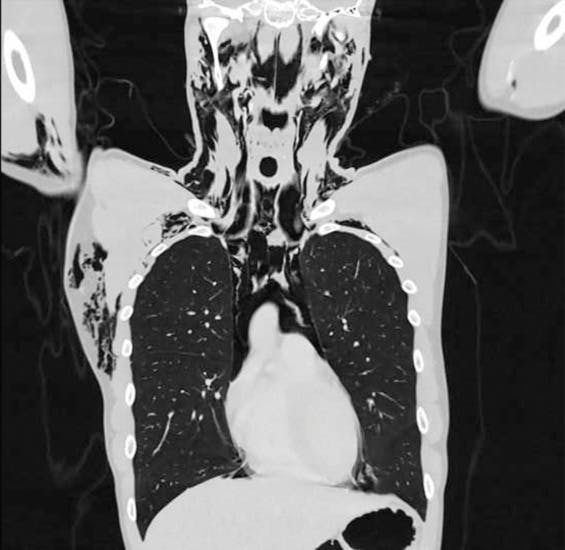

Røntgenbilleder viste, at manden havde fået spontan pneumomediastinum (SPM). Det er en sjælden lidelse, hvor luft siver ud af lungerne og sidder fast i bindevævet mellem lungerne.

Lægerne kategoriserede hans SPM som "voldsom", da en stor mængde luft havde hobet sig op i hans væv. Efterfølgende opdagede lægerne, at luften var vandret op i hans hals og hoved, så hans ansigt svulmede op.